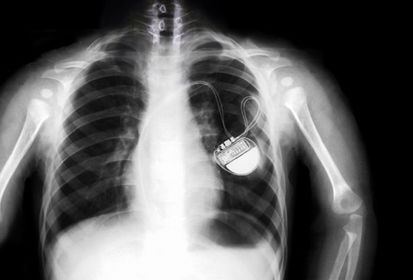

es un dispositivo que se coloca por intervencion quirurgica,desencadena la contraccion intrincesa, y sustituye el nodulo sinoauricular marcapaso artificial

son pequeños dispositivos que se colocan debajo de la piel por debajo de la auricula de forma similar a los marcapasos, un sistema de desfibrilacion monitorizada continuamente el ritmo cardiaco desfibrilador automatico implantable desfibrilador interno DAI